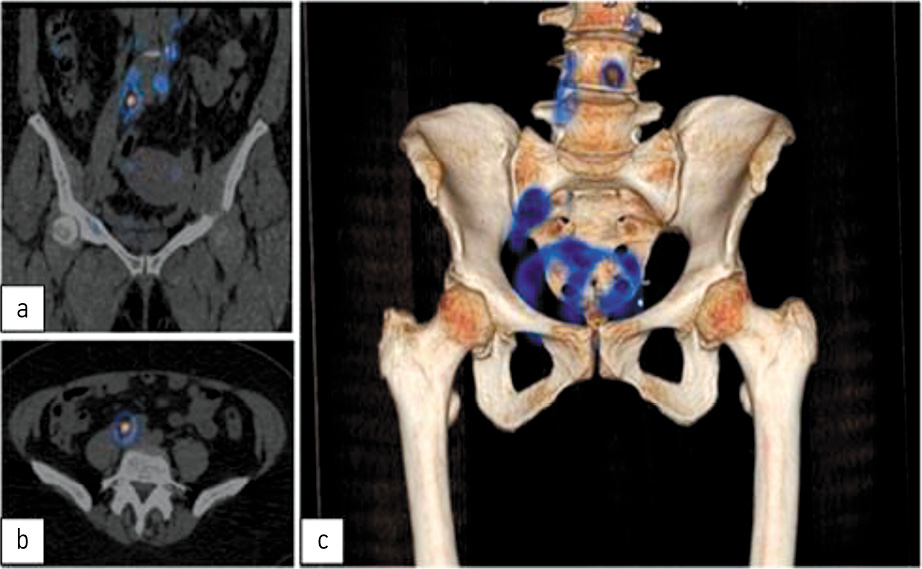

Через 2 ч после введения РФП выполнена однофотонная эмиссионная компьютерная томография (ОФЭКТ/КТ) брюшной полости и таза на аппарате Discovery 670 DR (GE) с последующей 3D-реконструкцией изображений для интраоперационной навигации (рис. 3).

Рис. 3. ОФЭКТ/КТ брюшной полости и таза пациентки Ч. во фронтальной (а), аксиальной (b) проекциях и 3D-реконструкция (c). На снимке (а) видно место введения РФП, небольшое накопление в мочевом пузыре, а также накопление РФП лимфатическими узлами таза. Справа определяется цепочка лимфатических узлов с максимальным накоплением РФП первыми двумя лимфатическими узлами, при измерении SUVmax уровень накопления в них составил 308, в двух других уровень значительно ниже – SUVmax до 38, в лимфатических узлах слева визуализирован один СЛУ с уровнем SUVmax до 240. На аксиальном снимке (b) и 3D-реконструкции (c) хорошо видна локализация СЛУ.